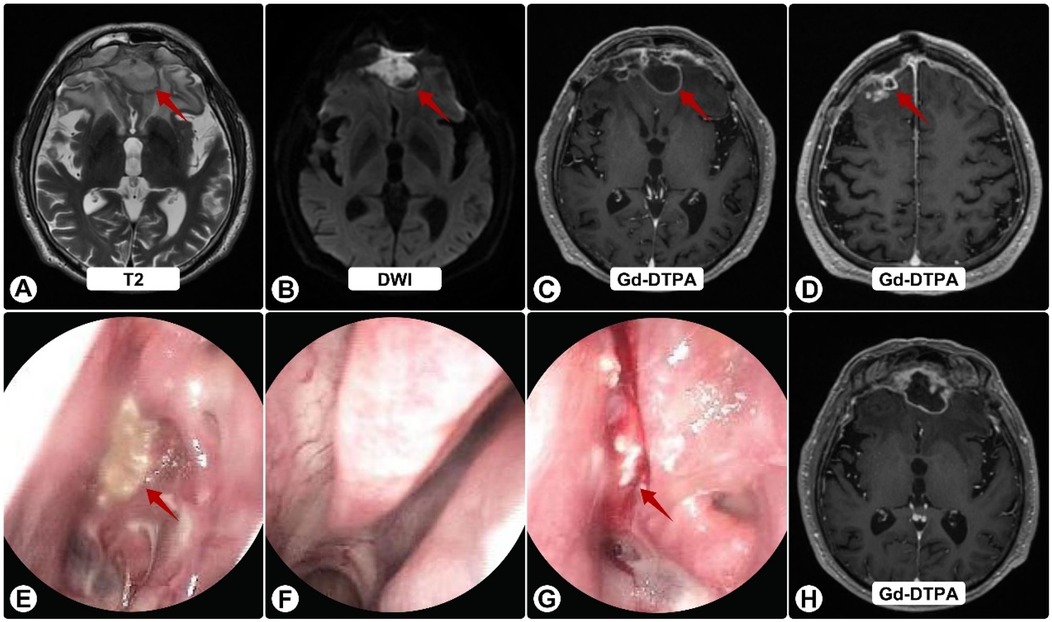

Two months thereafter he presented to our center. MRI demonstrated bilateral frontal lesions with extensive edema and ring enhancement (Figures 1A–F); nasal endoscopy confirmed purulence (Figures 1G–I). Pre-operative CT showed anterior skull-base sclerosis and erosion consistent with osteomyelitis (Figure 3A). Laboratory tests revealed leukocytosis with neutrophilia and mildly elevated CRP; HIV screening was negative. Serum galactomannan (GM) was negative.

Figure 1. Brain MRI and nasal endoscopy on admission. (A–F) White arrowheads indicate surrounding edema; red arrows show abscesses. MRI shows bilateral frontal lesions appearing hyperintense on T1 (A) and T2 (B), and isointense on FLAIR (C) Post-contrast images (D–F) reveal ring enhancement of lesions with extensive vasogenic edema and midline shift. (G–I) Nasal endoscopy shows purulent sinus secretions (red arrows).

Postoperatively, he received vancomycin and ceftriaxone plus fluconazole (guided by early nanopore reads suggesting possible Candida). He was discharged to complete IV antibiotics and fluconazole. Two weeks later he worsened neurologically. Follow-up MRI showed progression with persistent ring enhancement and diffusion restriction (Figures 2A–D); endoscopy again revealed purulence (Figures 2E–G).

MRI and endoscopic images display a brain and sinus evaluation. Panels A-D show axial brain scans highlighting abnormal areas with red arrows, labeled T2, DWI, and Gd-DTPA. Panels E-G depict sinus endoscopy images, with arrows pointing to areas of concern. Panel H is a Gd-DTPA MRI without visible arrows.

Figure 2. Follow-up brain MRI and nasal endoscopy. (A) T2-weighted image showing enlargement of frontal lesions (red arrows) with increased edema. (B) DWI shows persistent restricted diffusion. (C,D,H) Gd-DTPA–enhanced images demonstrate continued ring enhancement, with some solid components (H), (E–G) Endoscopy reveals persistent purulent secretions (red arrows) on the nasal mucosa (E), left middle meatus (F), and sphenoid sinus ostium (G), despite antibiotics.